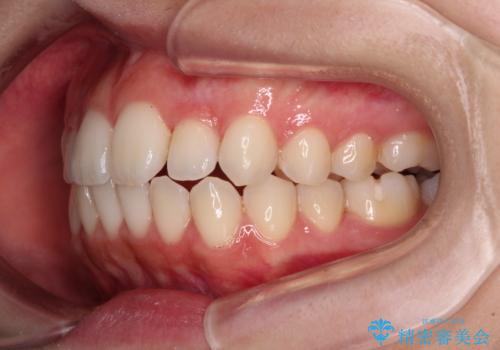

【モニター】前歯のクロスバイトをインビザラインで治療

- 前歯のデコボコとクロスバイトを気にして来院された患者様です。

上顎側切歯(上の真ん中から2番目の歯)が舌側転位している場合、インビザラインでは仕上げきれないことが多く、更には無理して動かそうとすると歯髄壊死を起こすリスクが高いと言われています。

今回は、ワイヤー装置を併用することなく、インビザライン単体で矯正治療を行うこととしました。

インビザライン特有の、奥歯の咬み合わせの問題もなく、しっかりと歯列を改善することができました。

舌側転位している上顎側切歯(内側に引っ込んでいる真ん中から2番目の歯)は、インビザラインが最も移動を苦手とする歯であり、これ以上の改善を望まれる場合にはワイヤー矯正、あるいはワイヤー矯正の併用をお勧めいたします。